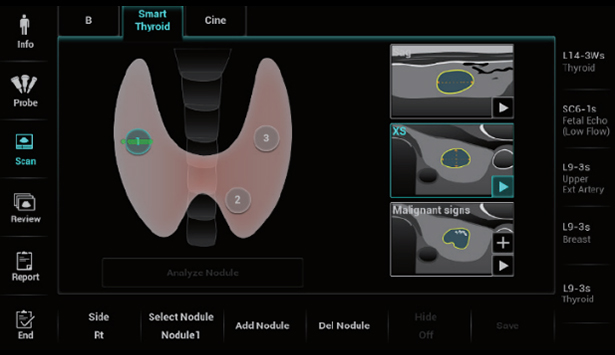

Zaawansowana diagnostyka